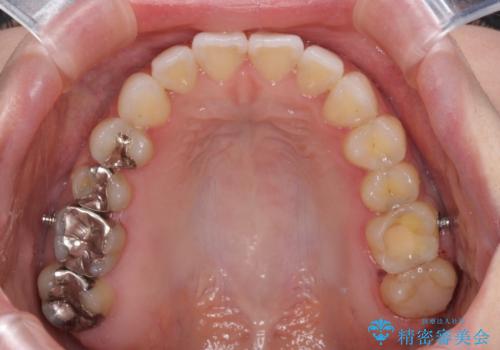

前歯のデコボコをすっきりと インビザライン矯正

- 前歯のデコボコを治したいとのことで来院された患者様です。

下顎が前方位にある方であったため、下顎の歯列全体の後方移動とIPR(歯と歯の間を削る)によってデコボコが解消するように設計し、インビザラインにより治療を行うこととしました。